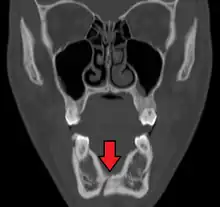

Computed tomography

Computed tomography is the most sensitive and specific of the imaging techniques. The facial bones can be visualized as slices through the skeletal in either the axial, coronal or sagittal planes. Images can be reconstructed into a 3-dimensional view, to give a better sense of the displacement of various fragments. 3D reconstruction, however, can mask smaller fractures owing to volume averaging, scatter artifact and surrounding structures simply blocking the view of underlying areas.

| 3D computed tomographic image of a mandible fracture in two places. One is a displaced right angle fracture and the other is a left parasymphyseal fracture. | |